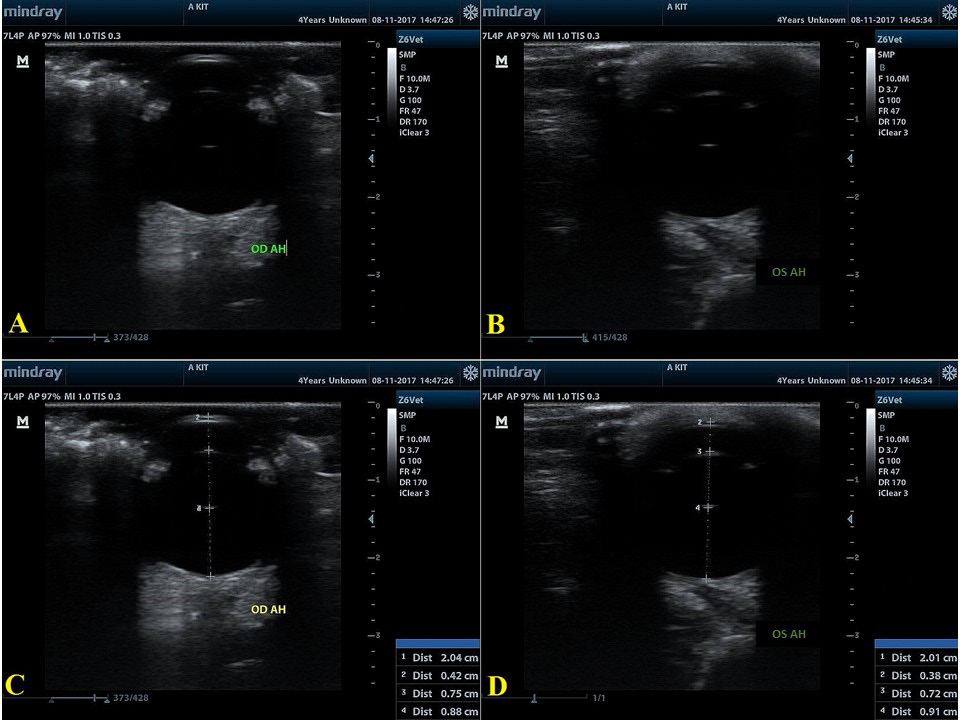

Ocular US evaluation in a female French Bulldog. Delicately contained in sitting position. Blepharostase was manual, and the exam was performed after instillation of 1 drop of anesthetic eye drops and sterile gel was used as a means of contact, using the transcorneal method.

Representative B-scan ultrasonogram of female French Bulldog (A) and (B) representative B-scan ultrasonogram after optimal positioning was achieved and in (C) and (D) after the measures were done. Measurement values: Right eye (OD): (C) HAD = 2.04 cm (20.4 mm); ACD= 0.42 cm (4.2 mm); LT= 0.75 cm (7.5 mm); VCD= 0.88 cm (8.8 mm). Left eye (OS): (D) HAD= 2.01 cm (20.1 mm); ACD= 0.38 cm (3.8 mm); Lens Thickness= 0.72 cm (7.2 mm); VCD= 0.91 cm (9.1 mm).